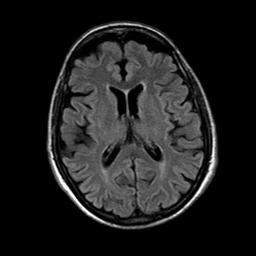

Radiological images: